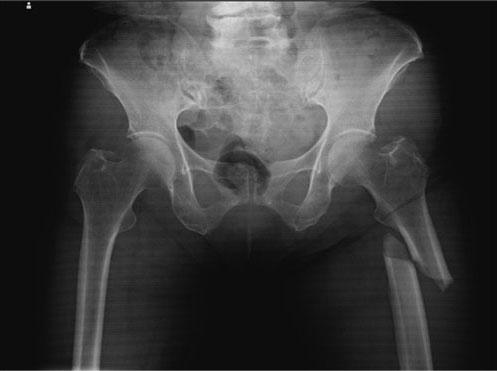

75歳の女性。交通事故により受傷。救急搬送時のエックス線写真を示す。遠位骨片を短縮転位させる主な筋はどれか。

yNmegBAKWZ75o5vp9qXej

1

中殿筋

2

小殿筋

3

腸腰筋

4

上双子筋

5

大腿直筋